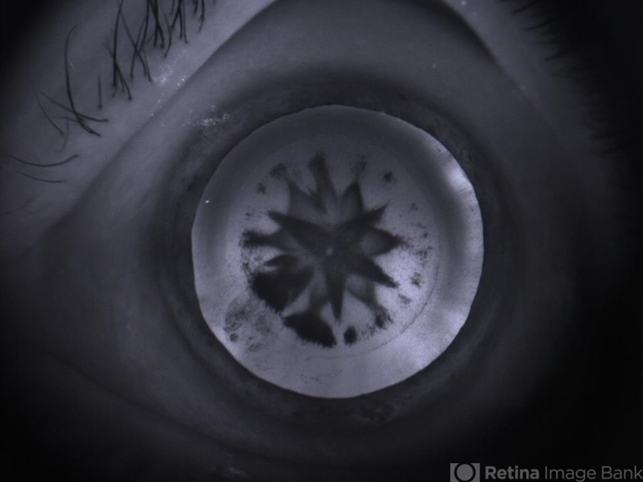

- developmental cataract, pediatric cataract

- A 9-year-old girl has presented with complaint of diminished vision ou. On retro illumination this image was captured.